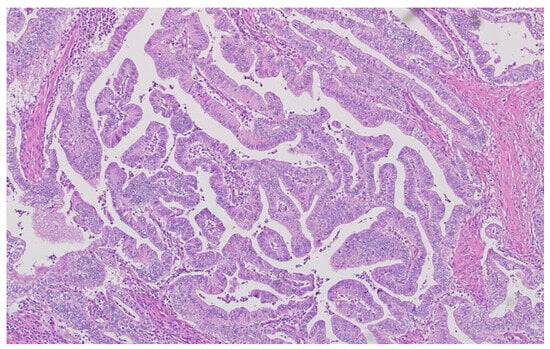

Hematoxylin–eosin staining was used for the direct exposure of the histopathologic subtypes (according to the WHO classification) present in the studied group, as shown in optical microscopy images.

Representative histopathological images of different tumor types are shown in Figure 2, Figure 3, Figure 4, Figure 5, Figure 6 and Figure 7, illustrating the histological subtypes observed in our cohort.

Figure 4. Mucinous adenocarcinoma with abundant extracellular mucin pools surrounding malignant glands (H&E, ×100, scale bar = 200 μm).